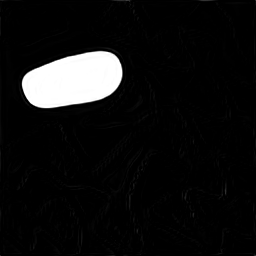

A few sample images and the corresponding masks of the polyp dataset in HyperKvasir are shown in Fig 2. The polyp images are RGB images. The masks of the polyp images are single-channel images with white () for true pixels, which represent polyp regions, and black () for false pixels, which represent clean colon or background regions. In this dataset, there are different sizes of polyps. The distribution of polyp sizes as a percentage of the full image size is presented in the histogram plot in Fig 3, and we can observe that there are more relatively small polyps compared to larger polyps. Additionally, a subset of this dataset was used to prove that the performance of segmentation models trained with small datasets can be improved using our SinGAN-Seg pipeline, and the whole dataset was used to show the effect of using SinGAN-Seg generated synthetic images instead of a large dataset which has enough data to train segmentation models. In this regard, this dataset was used for two purposes:

In total, we have generated synthetic polyp images and the corresponding masks. SinGAN-Seg generates random samples with high variations when the input scale is . This variation can be easily recognized using the standard deviation (SD) and the mean mask images presented in Fig 5. The mean and SD images were calculated by stacking the generated mask images corresponding to the synthetic images related to a real image and calculating pixel-wise std and mean. Bright color in std images and dark color in mean images mean low variance of pixels. In contrast, dark color in std and bright color in mean images reflect high variance in pixel values. By investigating Fig 5, we see that small polyp masks have high variance compared to the large polyp mask as presented in the figure.